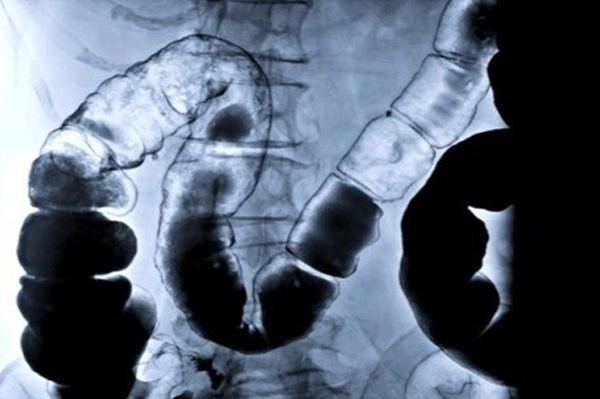

Cụ thể để "làm sạch" đại tràng bằng cà phê, các video này hướng dẫn người xem dùng cà phê loại "chuyên dụng dành riêng cho việc thải độc đại tràng" rồi đun sôi với nước lọc.

Nước cà phê được cho vào túi rồi được treo cao lên, thậm chí cả một xô nước, trong khi đầu dây còn lại cắm vào hậu môn. Lúc này, người thực hiện nằm thả lỏng, có thể tập thể dục nhẹ nhàng để dung dịch nước cà phê chảy vào cơ thể. Sau khi truyền hết túi dung dịch có thể xoa bụng và đi vệ sinh để thải bỏ toàn bộ cặn bã trong cơ thể ra ngoài.

Làm thụt rửa nhiều lần có thể dẫn đến viêm bỏng thành niêm mạc bên trong ruột, dẫn đến hoại tử phải cắt bỏ ruột như một vài ca bệnh do dùng thụt rửa cà phê đã công bố.

Chuyên gia cho hay việc tự tháo thụt không theo yêu cầu của bác sĩ có thể làm tổn thương cơ thắt hậu môn, viêm, chảy máu hoặc thủng rách trực tràng, chưa kể thành phần được bơm vào trực tràng có ảnh hưởng đến niêm mạc đại trực tràng hay không cũng chưa rõ.